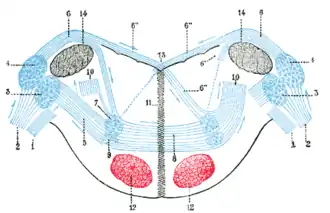

Unlike persistent vegetative state, in which the upper portions of the brain are damaged and the lower portions are spared, locked-in syndrome is essentially the opposite, caused by damage to specific portions of the lower brain and brainstem, with no damage to the upper brain. Injuries to the pons are the most common cause of locked-in syndrome.